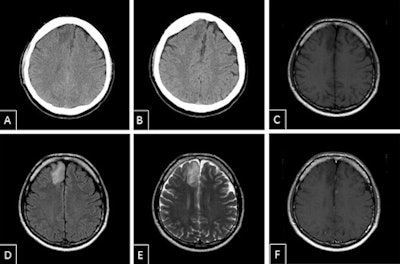

As part of a larger clinical study on whole-body CT, radiologists in Berlin have now taken a closer look at these secondary findings. The radiologists reported the first results during RöKo 2016. For example, of the total of 518 patients who underwent a whole-body CT scan between September 2014 and April 2015, almost 300 (57.9%) presented with secondary findings. Every 10th patient required immediate treatment.

"Among them were cases of previously undetected acute pneumonia and inflammation of the pancreas, as well as tumors of the lung and brain," Kahl said.